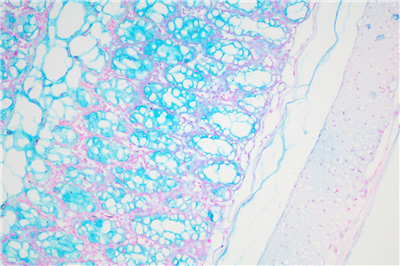

阿利新藍(lán)(又稱阿爾辛藍(lán)﹑愛先藍(lán)等)和PAS技術(shù)聯(lián)合使用可鑒別同一組織中的中性黏蛋白和酸性粘蛋白。這種技術(shù)也常用作廣泛檢測黏蛋白的手段,切片先經(jīng)標(biāo)準(zhǔn)阿利新藍(lán)染色再使用PAS技術(shù)。阿利新藍(lán)可將唾液黏蛋白﹑硫黏蛋白和蛋白多糖染成藍(lán)色。PAS技術(shù)可將中性黏蛋白染成深紅或紫紅色,同時(shí)將既含中性黏蛋白又含酸性黏蛋白的組織和細(xì)胞染成深淺不同的紫色,這是由于阿利新藍(lán)與Schiff試劑結(jié)合并發(fā)生反應(yīng)。上述染色??沙霈F(xiàn)在含有中性黏蛋白和唾液黏蛋白的笑場杯狀細(xì)胞中。阿利新藍(lán)的染色原理在于是類銅鈦花青染料,這種陽離子染料與酸性基團(tuán)結(jié)合,也即阿利新藍(lán)與組織內(nèi)含有的陰離子基團(tuán)如羧基和硫酸根形成不溶性復(fù)合物。分子中帶正電荷的鹽鍵與酸性粘多糖物質(zhì)中帶負(fù)電荷的酸性集團(tuán)結(jié)合形成不溶性的復(fù)合物而呈藍(lán)色,再與PAS進(jìn)行復(fù)合染色,就能顯示三種不同黏液物質(zhì)成分。